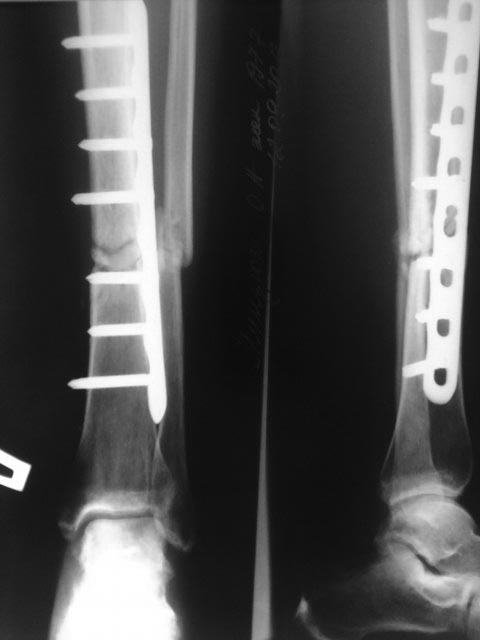

Псевдоартроз лечат исключительно оперативным путем. Хирурги иссекают фиброзную и хрящевую ткань, расположенную между костными фрагментами. Затем они заново сопоставляют отломки и фиксируют их системами чрескостной, накостной или интрамедуллярной фиксации. После этого пациент проходит полноценную реабилитацию.

Для стабилизации костных фрагментов могут использовать такие приспособления:

- аппарат Илизарова;

- штифты;

- винты;

- накостные пластины;

- интрамедуллярные стержни.

«Золотым стандартом» лечения псевдоартроза считается пересадка донорских или аутологичных кровоснабжаемых костных трансплантатов. Как правило, их получают из гребня подвздошной кости. Фрагменты костной ткани хорошо приживаются и не образуют фиброзных рубцов в месте пересадки.